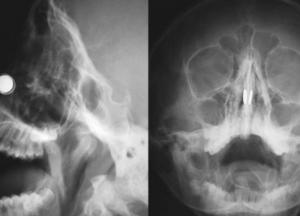

Сперва он прицепил магниты к мочкам ушей, а потом засунул пару магнитов в нос, соединив их с другой парой, закрепленной снаружи носа. Но, когда он снял внешнюю пару, внутренняя соединилась и застряла. Ученый попытался вытащить ее при помощи двух оставшихся магнитов, но и эта затея провалилась. После 20 минут безуспешных попыток и беглого поиска в интернете он нашел решение – использовать больше магнитов. Он взял два оставшихся и сосредоточился на левой ноздре.

"Я тянул, пытаясь вытащить магниты, но они выскочили из моих рук и сцепились, - рассказал Рирдон. – Два магнита застряли в моей левой ноздре, а еще один засел в правой. К этому моменту магниты у меня закончились".

Предприняв еще пару неудачных попыток достать запчасти от своего изобретения, доктор сдался и отправился больницу. Медики извлекли 3 магнита из левой ноздри, после чего магнит в правой выпал сам. Хотя эпопея могла и на этом не закончиться, ведь, по словам Рирдона, в этот момент он едва не поперхнулся.